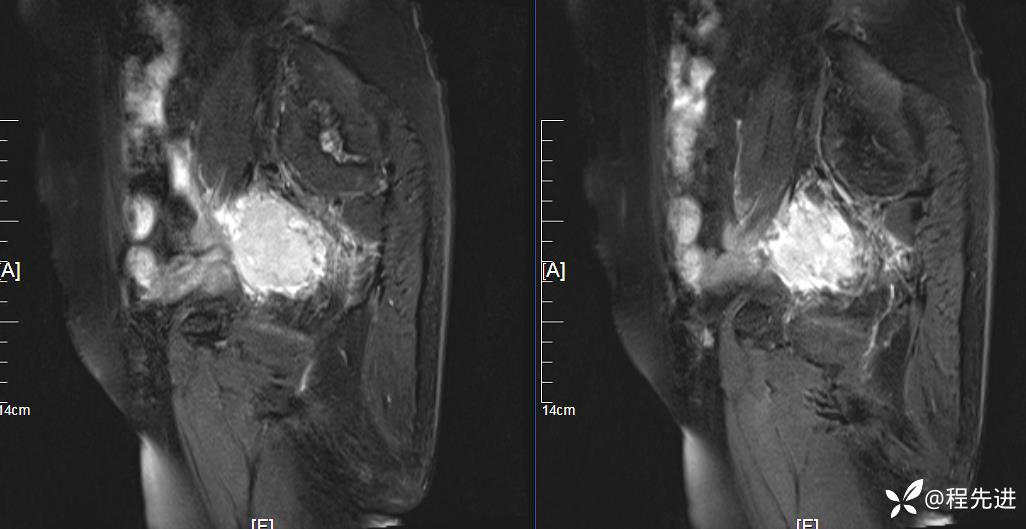

MRI平扫:

T2压脂:

T2:

T1:

患者性别:女

患者年龄:76岁

简要病史:下腹痛伴发热半月余

实验室检查:肿瘤指标均正常